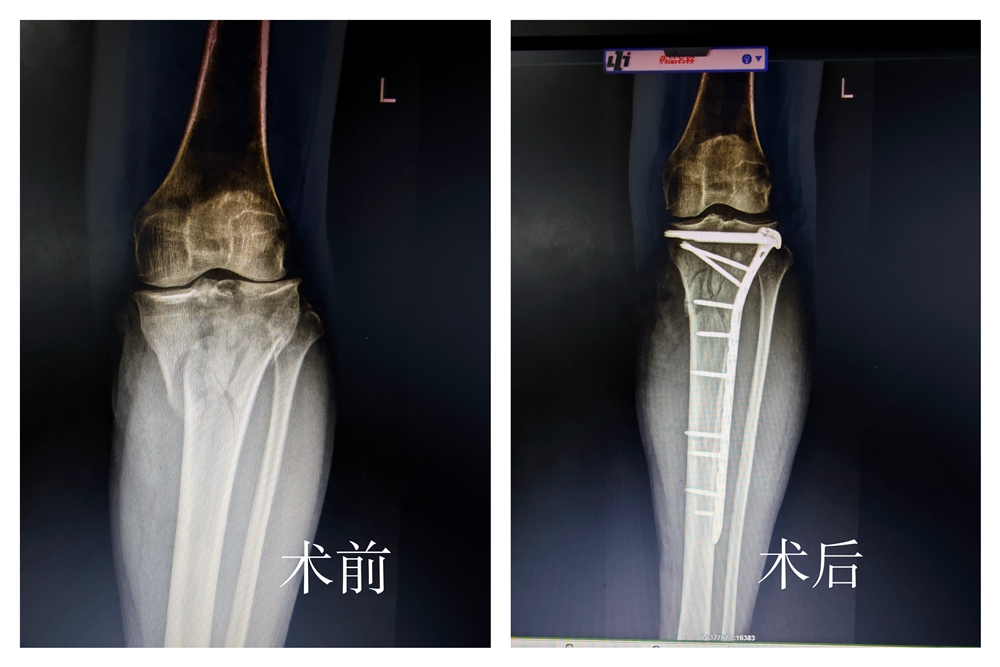

4月1日,刘女士因意外摔伤导致左膝流血不止,剧烈肿痛、活动受限,被紧急送往县中医院。经骨一科陈美富医生详细检查,诊断显示:左胫骨髁间隆突、外侧平台及腓骨头骨折,前后交叉韧带损伤,内侧半月板后角损伤(Ⅱ°),外侧半月板信号消失,髌上囊及关节腔大量积液,同时伴有左侧腘肌、胫骨后肌损伤及皮下软组织积血,胫前内侧开放性创口。伤情复杂,治疗难度较大。

入院后,陈美富医生急诊清创后第一时间为患者完善检查,制定个性化治疗方案:患肢持续骨牵引外固定制动,予以消肿止痛等对症处理。待局部肿胀明显消退、身体条件符合手术标准后,于4月6日在会诊麻醉下,顺利为患者实施“左侧胫骨平台骨折切开复位内固定+植骨术”。术中钢板植入位置精准,术后复查影像显示骨折复位满意。